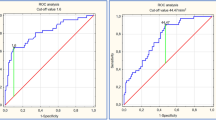

Diagnostic performance: ROC analyses

The receiver operator characteristics (ROC) curves demonstrated that the E:e’ and e’ velocity have good discriminatory capacity in predicting LAAT with respective areas under the curve (AUC) of 0.72 and 0.74, which trended to be larger than the 0.65 AUC associated with the CHADS2 score (P = 0.17 and 0.052, respectively), as shown in Figure 4. In this population, the ROC curve point-coordinates identified an E:e’ value of ≥9.4 to have 100% sensitivity and 38% specificity for LAAT; whereas E:e’ ≥ 15 was associated with a specificity of 78% at the expense of a low sensitivity (32%). An e’ velocity ≤10 cm/sec was associated with 100% sensitivity for LAAT (Figure 4). Only a CHADS2 score of zero was “protective” from LAAT.

Receiver operating characteristic curves. AUC: area under the curve; CI: confidence intervals. The receiver operating characteristic curves associated with the E:e’ ratio and CHADS2 score were not statistically different (P = 0.17); whereas the difference between the curves associated with e’ velocity and the CHADS2 score was borderline significant (P = 0.07).